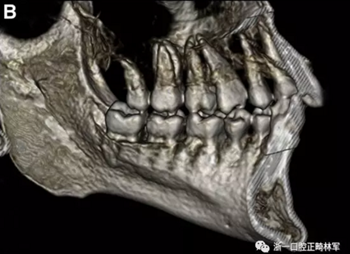

患者的上頜骨和下頜骨研究模型在最大牙尖交錯位時確定和數(shù)字化(圖2,A),作為咬合指導(咬合指導)。該數(shù)字化咬合指導在齦緣周圍進行數(shù)字化修剪,以便在CBCT掃描上可以更好得可視化(圖2,B)。

圖2. A,咬合時對象研究模型的右側舌側視圖掃描將作為未來指導;該指導稍后用于將懸浮的下頜骨配對到修剪的上頜骨;B,左側舌側視圖的數(shù)字化修整牙合引導。